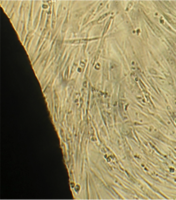

Исследование проведено на первичных культурах дермальных фибробластов и мезенхимальных стромальных клетках человека 4-12 пассажа.

Культуру дермальных фибробластов получали из кожно-мышечной ткани, а культуру мезенхимальных стромальных клеток – из фрагментов крыши черепа абортусов сроком 6-10 недель методом первичных эксплантатов (рис. 1, 2).

Клетки культивировали в стандартных условиях в термостате Sanyo – Incubator MIR-262 при температуре 37°С в среде МЕМ с 10% эмбриональной телячьей сыворотки в пластиковых культуральных флаконах Orange Scientific (производство Бельгии), Corning (производство США) площадью 25 и 75 кв. см. Тестирование производили в культуральных чашках Петри Sarstedt диаметром 3 см (рис. 3).